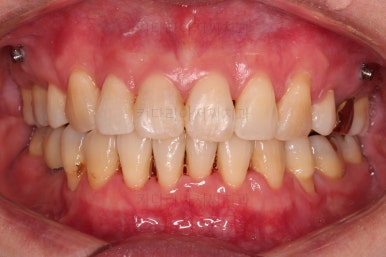

오늘 동래임플란트교정 키다리아저씨치과에서 소개해 드릴 환자분은 돌출입과 삐뚤어진 치열을 가지런하게 하고 싶었던 분이며 입 안에는 이미 임플란트가 되어있었고, 해당 임플란트 상부 보철물을 수정해야 했던 환자분입니다.

동래임플란트교정 초진 시 입안의 모습입니다.

치열이 전반적으로 삐뚤어져 있는 양상이고요.

아랫니가 윗니보다 더 많이 삐뚤어 있는데요.